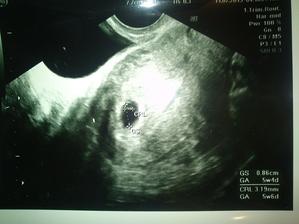

snad coskoro budu pribudat krasne fotky

mesiac maj nam nevysiel snad dalsi mesiac bude uspesny .